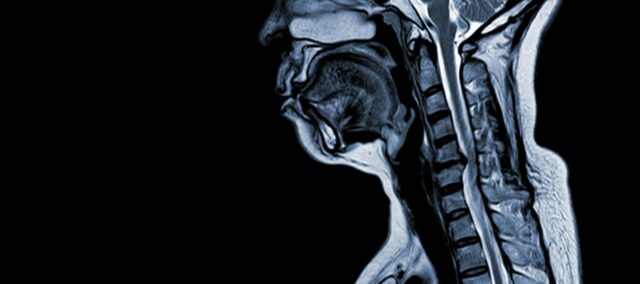

La myélopathie spondylaire cervicale (MSC) est une affection neurologique qui est la principale cause de lésion de la moelle épinière chez l'adulte. En termes simples, il s'agit d'une compression ou d'une lésion de la moelle épinière dans le cou, principalement due au processus naturel de vieillissement qui affecte les vertèbres cervicales. Le terme "myélopathie" provient des mots grecs "myelon", qui signifie "moelle épinière", et "pathos", qui signifie "maladie".

- Dégénérescence discale (bombement du disque) : La MSC commence souvent par la dégénérescence des disques intervertébraux de la colonne cervicale, qui se bousculent ou font saillie dans le canal rachidien.

- Formation osseuse sous-périostée (ventrale du canal rachidien): En réponse à un stress mécanique accru, le corps forme un nouveau tissu osseux sur la face avant (ventrale) du canal rachidien, ce qui risque de rétrécir l'espace réservé à la moelle épinière.

- Ossification du ligament longitudinal postérieur : Le ligament longitudinal postérieur peut s'ossifier, se durcir et se calcifier, contribuant ainsi au rétrécissement du canal rachidien.

- Hypertrophie du ligamentum flavum : L'hypertrophie du ligamentum flavum entraîne son épaississement et sa perte de souplesse, ce qui empiète davantage sur l'espace du canal rachidien et comprime la moelle épinière.

Ces changements structurels conduisent collectivement à la compression et au rétrécissement du canal rachidien, ce qui entraîne les symptômes et les complications caractéristiques de la MSC. La reconnaissance de ces facteurs de risque et la compréhension des mécanismes physiopathologiques impliqués sont essentielles pour la prévention et la prise en charge. Un diagnostic précoce et des interventions appropriées sont essentiels pour atténuer les effets de ces altérations structurelles sur la moelle épinière.